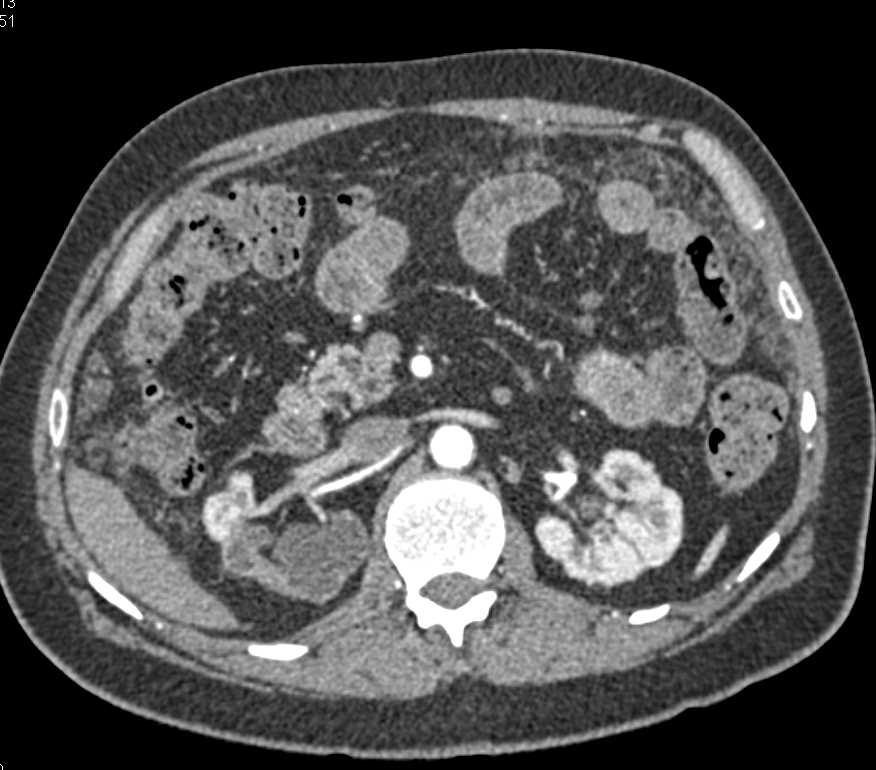

Colitis Involving the Right Colon with CT Angiography